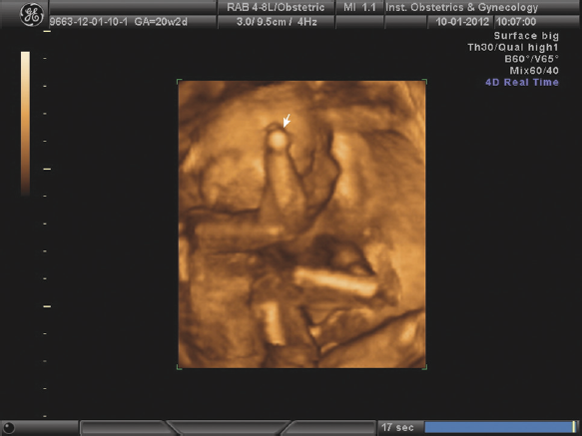

Рис. 2. Редукция правой кисти плода, 17 недель беременности

Преобладающее большинство особенностей развития было выявлено в первой половине беременности (до 80 %), причем 30 % из них — в I триместре (табл. 2). За период с 2013 по 2017 г. наметилась тенденция к увеличению числа пороков развития, обнаруженных в I триместре. За исследуемый период значительно выросла частота выявления в I триместре таких пороков, как хейлогнатопалатосхизис, полидактилии, редукционные пороки конечностей (рис. 1, 2). По нашему мнению, значительно увеличить процент диагностики пороков развития возможно при более раннем обращении (I триместр) в учреждения экспертного уровня.